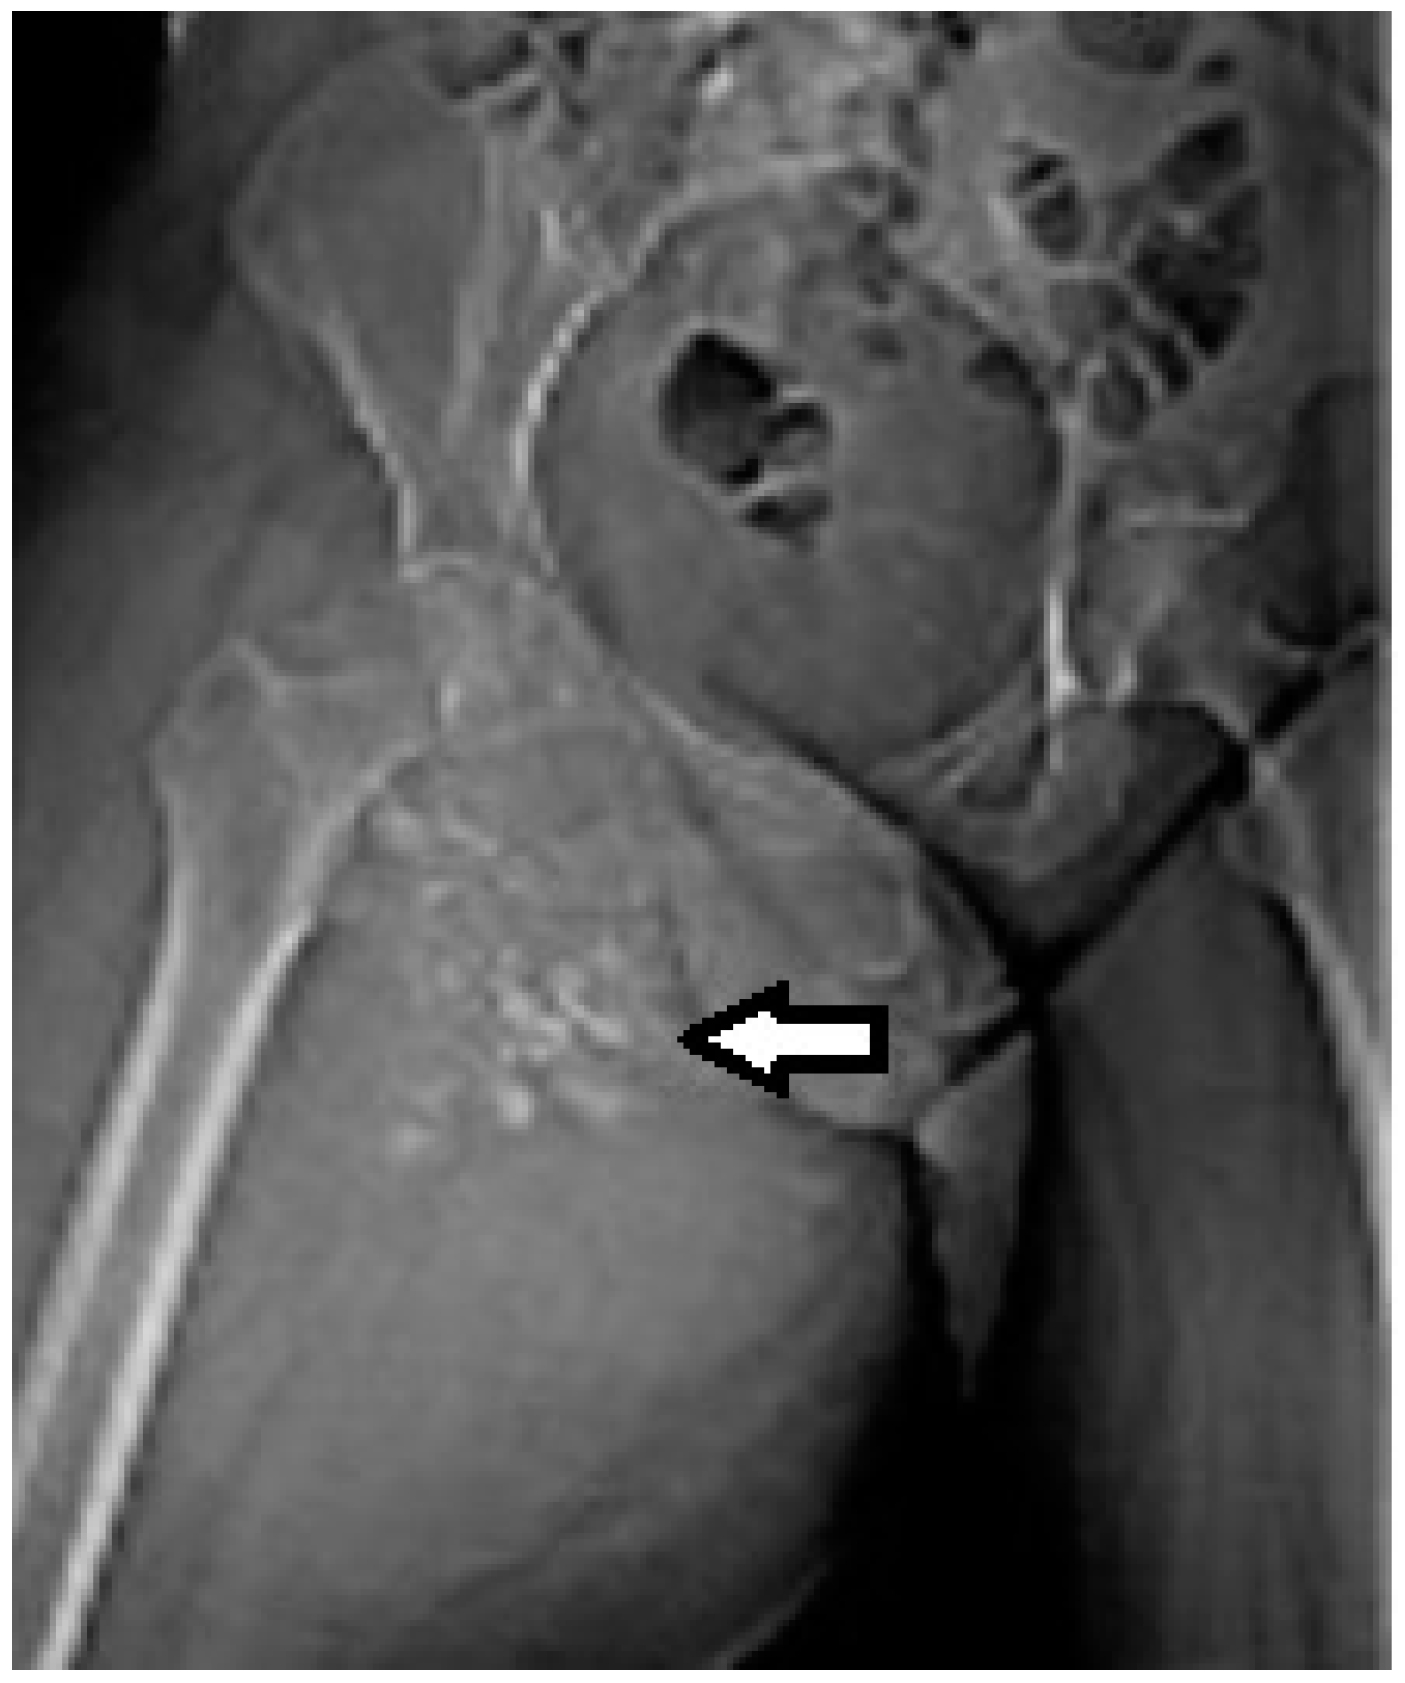

Magnetic resonance imaging (MRI) with contrast should be considered for tumors exceeding 2–3 cm and is probably the imaging method of choice for synovial sarcomas. MRI will provide valuable information regarding the extent of the tumor and the relationship with the surrounding anatomical structures; the use of a gadolinium contrast will enhance the amount of information that can be obtained since it is able to differentiate between hemorrhagic areas and solid tumoral tissue.

The T2 sequences are more specific for the diagnosis of soft tissue sarcomas and can reveal an inhomogeneous tumor, mainly with a hyperintense signal, in contrast with muscles, and the specific “triple sign” is present, representing a mixture of solid parts (medium hemorrhage and/or necrosis (high signal intensity) and calcifications or/and fibrotic areas (low signal intensity). The heterogeneity is completed by the presence of cystic parts with an aspect of fluid–fluid levels due to blood sedimentation (Figure 2 and Figure 3).

Figure 2.

A 40-year old female patient with synovial sarcoma. Image represents an axial MRI of the proximal right thigh—axial T2 FSE (fast spin echo) and FATSAT (fat saturation). There is an increased diameter of the right thigh because of a soft tissue mass (thin arrows), where an inhomogeneous mixture of solid and cystic areas is shown (block arrow).

Figure 3.

Same patient as in Figure 1 and Figure 2, MR image, coronal T2 STIR (short-time inversion recovery): heterogeneous soft tissue mass showing a mixture of solid areas (line arrow), hemorrhage and/or necrosis (block arrow), calcifications or fibrosis, cystic elements and infiltration of adjacent fat. Furthermore, fluid–fluid levels (block arrow) can be observed in this figure.